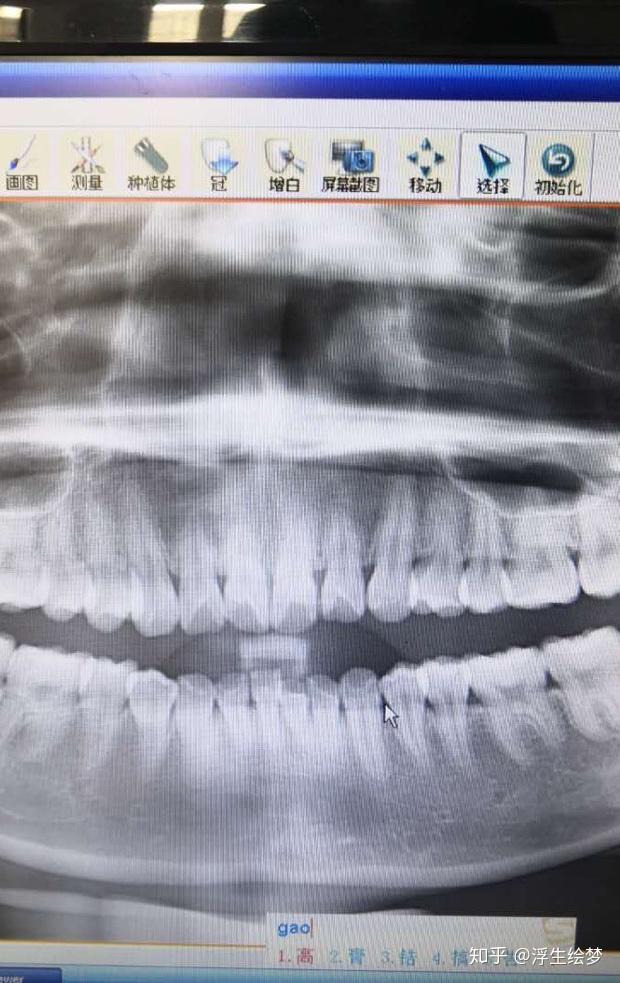

uu们看看牙牙牙根这么短可以矫正嘛而且牙槽骨也薄

图片尺寸1080x1440